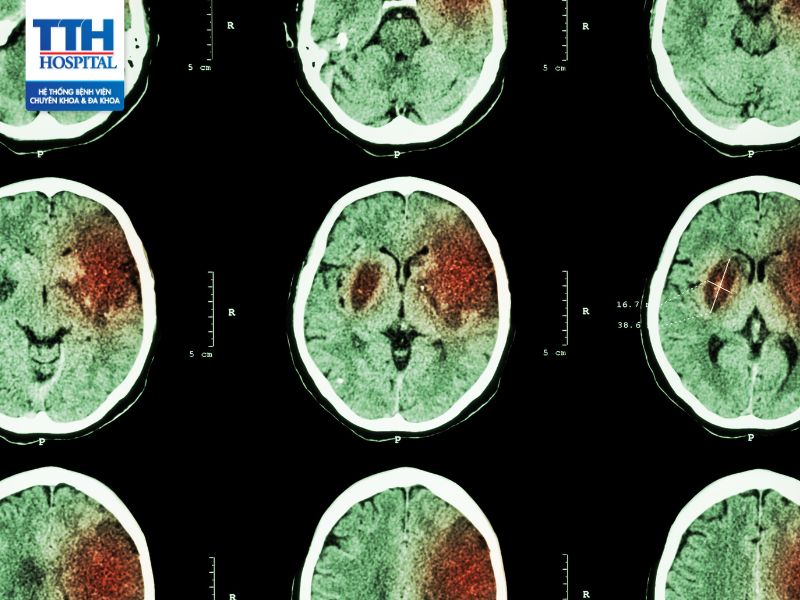

Tai biến mạch máu não hay còn gọi là đột quỵ được xem là một trong những bệnh lý nguy hiểm nhất, nguy cơ tử vong cao nếu không sớm nhận biết triệu chứng tai biến và can thiệp kịp thời.

Tai biến mạch máu não luôn là một thách thức đối với nền Y Học. Theo thống kê của tổ chức Y tế thế giới WHO, tỷ lệ tử vong do tai biến mạch máu não đang đứng thứ ba sau bệnh ung thư và tim mạch.

Tai biến mạch máu não còn được gọi là cerebrovascular accident (CVA) hoặc stroke, là tình trạng mạch máu cung cấp dưỡng chất và oxy tới một phần của não bị gián đoạn hoặc bị chặn hoàn toàn. Điều này có thể xảy ra do một quá trình gọi là động mạch bị tắc nghẽn (ischemic stroke) hoặc do sự vỡ nứt của mạch máu trong não (hemorrhagic stroke).

- Tai biến mạch máu não xuất huyết (Hemorrhagic stroke)

Loại này xảy ra khi một mạch máu trong não vỡ nứt, dẫn đến sự chảy máu vào mô não. Điều này gây áp lực lên các mô và tế bào xung quanh, gây ra thiệt hại vùng não và gây ra các triệu chứng như đau đầu cực mạnh.